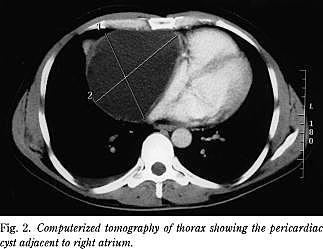

Patienten blev overflyttet til thoraxkirurgisk specialafdeling, hvor ovenstående blev bekræftet ved en CT (Fig. 2 ).

Ved røntgenundersøgelse af thorax fremtræder cysten som en velafgrænset homogen struktur. Diagnosen styrkes med TTE (8), som muliggør en opmåling af cysten og en afgrænsning fra hjertet. Yderligere afklaring sker ved transøsofagal ekkokardiografi og CT af thorax (9).